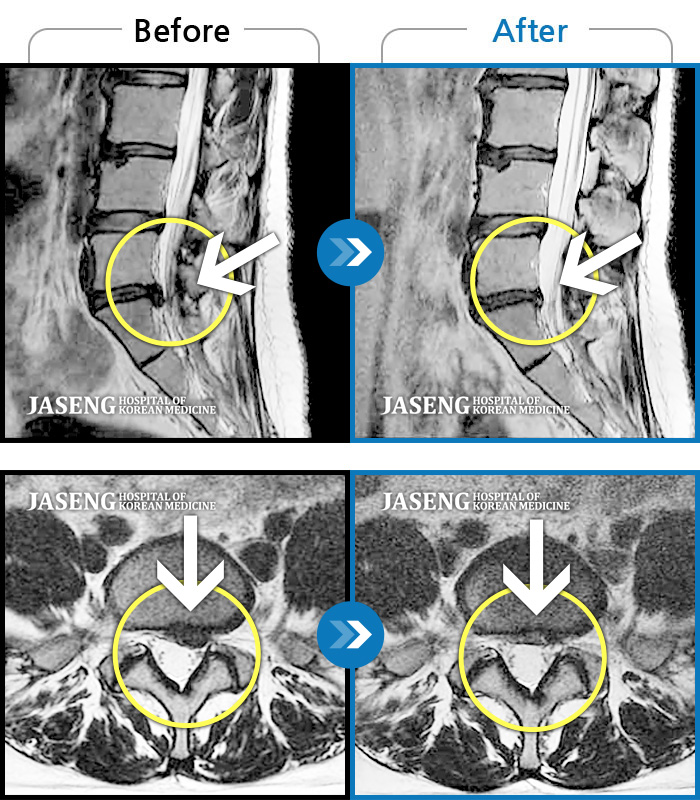

허리디스크

잠실 · 한상욱 원장

허리통증과 함께 좌측 엉치, 허벅지, 종아리 후면으로 저림이 심하여 걷기가 힘들어요.

촬영시기

2021.09.14 ~ 2022.05.14

2022.05.24